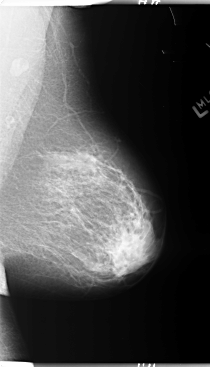

B_3095_1.LEFT_MLO

LEFT_MLO LINES 5864 PIXELS_PER_LINE 3360 BITS_PER_PIXEL 12 RESOLUTION 50 NON_OVERLAY